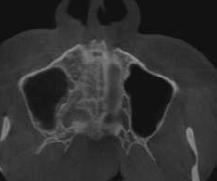

Estudios tomográficos en los cuales se observa tumoración expansiva a piso nasal de 3 centímetros de diá metro aproximadamente isodensa a tejidos blandos en zona de pala dar blando (Figura 3A y 3B). Motivo por el cual se decidió realizar biopsia incisional (Figura 4A , 4B y 4C) obte niendo un diagnóstico de Adenocar cinoma de células basales en paladar blando (Figura 5) con el cual se rea lizó referencia al centro oncológico naval para su seguimiento y trata miento. Actualmente se encuentra en tratamiento de quimioterapia.

Figura 3. Tomografía en corte axial con ventana ósea en la cual se observa paladar duro sin aparente afección ósea. Tomografía en corte sagital con ventana ósea en la cual se observa dimensiones aparentes de la tumoración en paladar blando. A B

El Dr. José Augusto Tuy de Britto menciona que la tomografía com putarizada ayuda a evaluar lesiones que afectan a los tejidos duros ya que permite ver diferentes cortes tomo gráficos con mínima distorsión de la imagen siendo el estudio indicado para delimitar la extensión de nues tra tumoración en el paladar blando, la cual se extiende hacia piso nasal y pared posterior faríngea.21